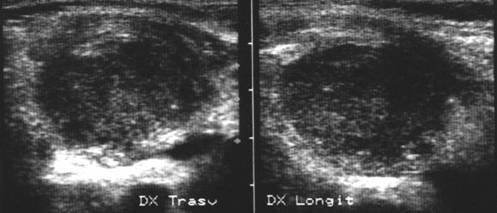

Aceeasi pacienta – piesa chirurgicala – lobectomie dreapta. Examen histologic:nodul hiperplazic